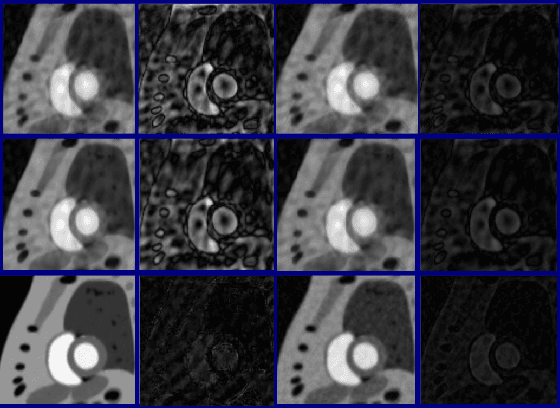

Abstract:We describe a method for verifying the output of a deep neural network for medical image segmentation that is robust to several classes of random as well as worst-case perturbations i.e. adversarial attacks. This method is based on a general approach recently developed by the authors called "Trust, but Verify" wherein an auxiliary verification network produces predictions about certain masked features in the input image using the segmentation as an input. A well-designed auxiliary network will produce high-quality predictions when the input segmentations are accurate, but will produce low-quality predictions when the segmentations are incorrect. Checking the predictions of such a network with the original image allows us to detect bad segmentations. However, to ensure the verification method is truly robust, we need a method for checking the quality of the predictions that does not itself rely on a black-box neural network. Indeed, we show that previous methods for segmentation evaluation that do use deep neural regression networks are vulnerable to false negatives i.e. can inaccurately label bad segmentations as good. We describe the design of a verification network that avoids such vulnerability and present results to demonstrate its robustness compared to previous methods.